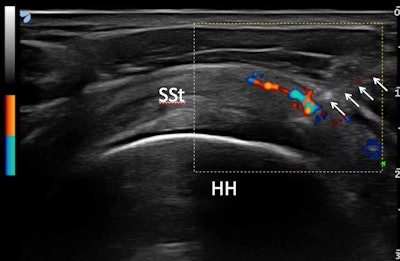

Ultrasound-guided injections of PRP in the supraspinatus tendon. Needle is shown with arrows and the spread of PRP is visible on color Doppler. All images courtesy of Dr. Francesco Arrigoni.Arrigoni noted that MRI findings provide important evidence of the therapy's effectiveness, serving to confirm the clinical evidence.